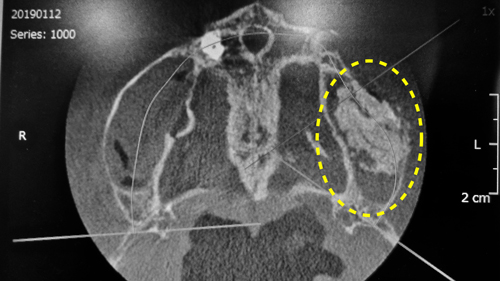

③頭上から観たCT断層写真

頭上から観たCT断層写真

想像以上に骨がガッチリと出来上がっていました。